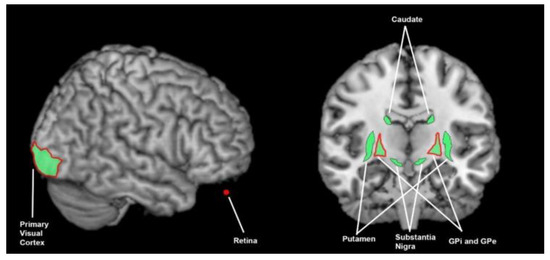

3.3.5. What Brain Areas Are Involved in Visual Processing in Healthy Cohorts?

3.3.6. What Brain Areas Are Found to Function Abnormally during Visual Processing in People with Parkinson’s Disease?

3.4. The Breadth of Sensory Response and Multisensory Response of the Basal Ganglia

4.1. What Brain Areas Are Involved in Sensory Processing, What Are the Abnormalities in Parkinson’s Disease, and What Is the Importance of the Basal Ganglia?

6.2. Difficulty Interrogating Deep Brain Nuclei for Sensory Function in Human Models